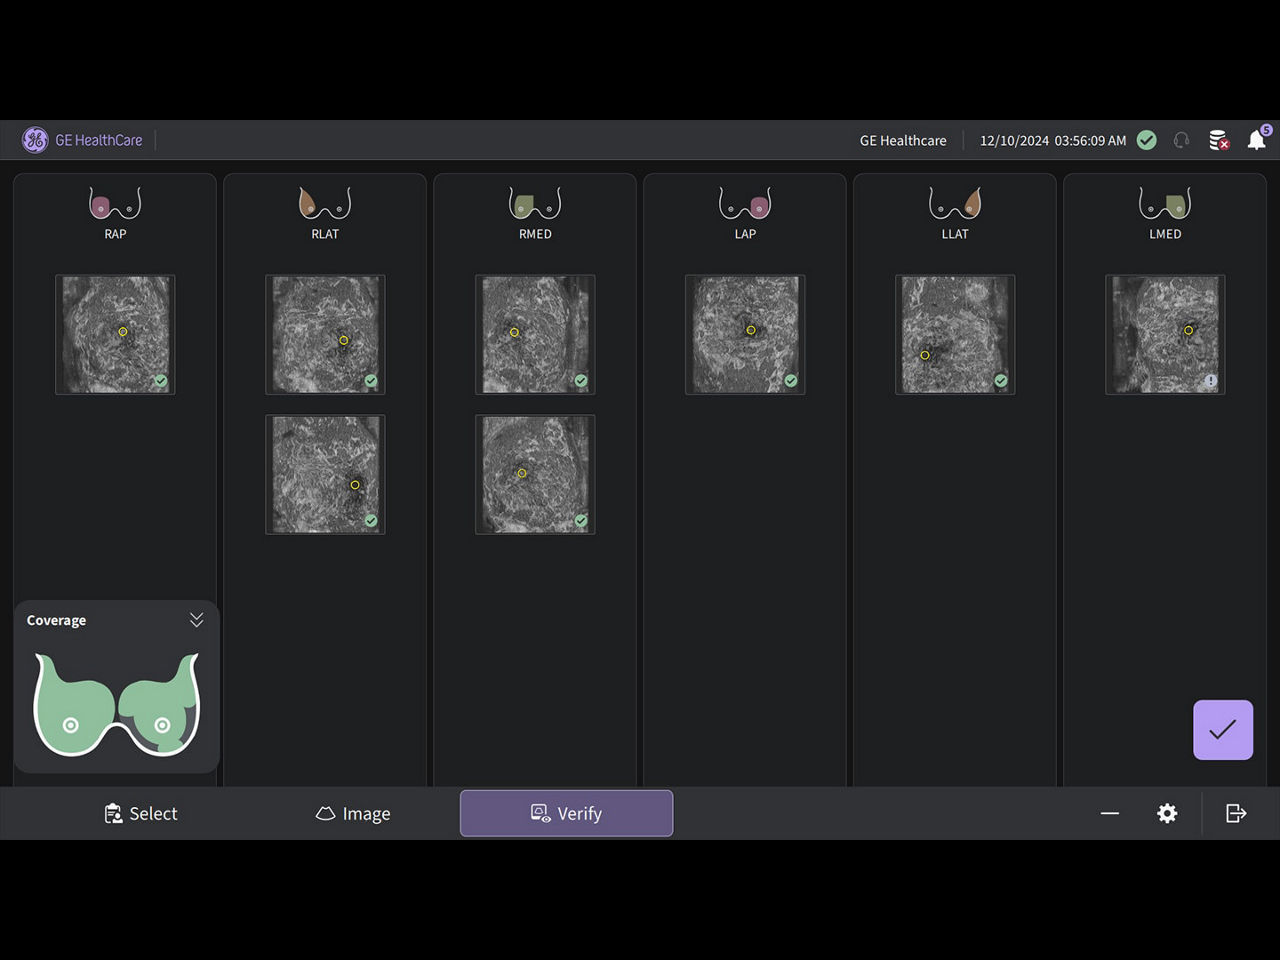

Productivity powered by AI

Boost clinical confidence and efficiency with AI-driven scanning and reading